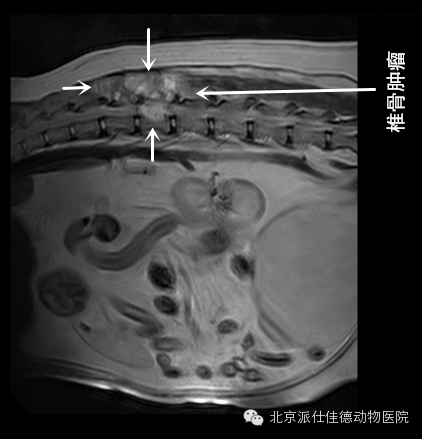

1.有些动物因为视力不好,按照是神经炎治疗,结果通过检查发现是脑肿瘤压迫视神经导致;

7.有些动物表现腰疼,一直按椎间盘突出治疗,结果经诊断为脊椎肿瘤或是椎管内肿瘤或是脊髓本身肿瘤引发。